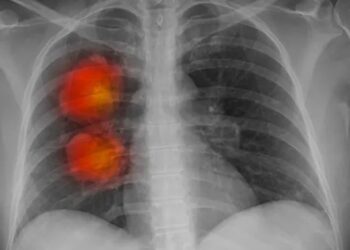

New artificial intelligence tool can accurately identify cancer

Exclusive: algorithm performs more efficiently and effectively than current methods, according to a study Doctors, scientists and researchers have built ...